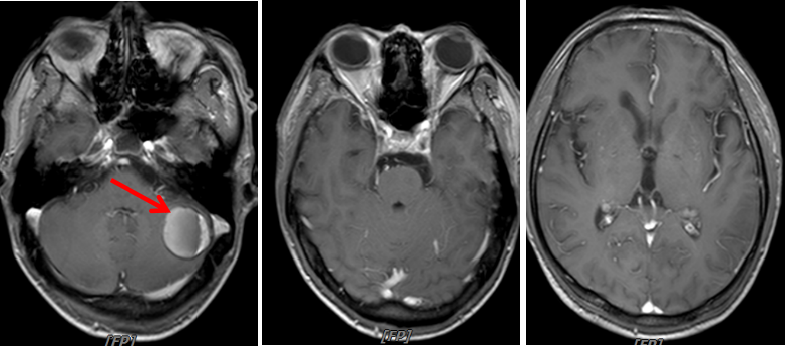

图7:2020年3月25日,联合治疗2周期后头颅MRI

图9:2020年5月6日,联合治疗4周期后头颅MRI

图11:2020年6月24日,联合治疗6周期后头颅MRI

本例患者为“左肺上叶小细胞癌(广泛期,cT3N1M1,IV期),伴左肺门淋巴结转移、多发脑转移”,考虑予以免疫联合化疗。为明确并监测患者可能出现的毒副反应,先予以患者1周期EP方案化疗,同时予以全脑放疗1个月。患者未出现明显不良反应,予以患者加用替雷利珠单抗免疫治疗2周期,疗效评价即达到PR,治疗6周期后疗效达到CR。随访至今PFS已超过7个月,疗效持续CR,安全性良好,患者可以耐受。